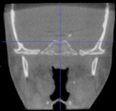

Three points determined the Acta plane: O, F right (FR), and F left (FL) (Table 2). Point O is the midpoint between the most craniodorsal point of the dorsum Sella and the most posterior dorsal point of the Basion in the midsagittal plane (Figure 1). Both points F are a result of the intersection between two lines: the line that connects the most inferior points of the lower orbital margins, right and left, and a line perpendicular to this line that runs through the most external points of the orbital margins, right and left (Figure 2). The new transverse reference plane, the Acta plane (Figure 2), is created by connecting the O-point (Figure 1) with FR and FL (Figure 2).

Figure 2.

(A) Construction of the F-points (right and left), frontal view. The F-points are originated from the intersection between the line connecting points A (the most inferior point of the lower orbit) and the perpendicular line to it that passes through points B (most external/lateral point of the Orbita). (B) Transverse view of the ACTA plane.